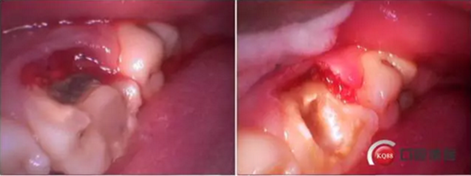

牙列完整,后牙中性關(guān)系,前牙開合,中線對(duì)齊。16合面大面積齲壞,內(nèi)褐色腐質(zhì),冷診無反應(yīng),叩痛(+-)。36合面樹脂充填,充填物在位,頰側(cè)冠折,折線位于齦緣下,冷診無反應(yīng),叩痛(+)。其他無殊。

診斷:36冠根折。

這是折線的位置,右是拔出的牙齒碎片。很明顯折裂波及遠(yuǎn)中頰根。

先去了充填物,去腐,牙齦電切。根折根上段少量,沒有破壞根管結(jié)構(gòu)。選擇保留患牙。

牙齦切除后,根折面平整拋光,恢復(fù)頰側(cè)壁。

牙齦電刀切除,樹脂做頰側(cè)壁。